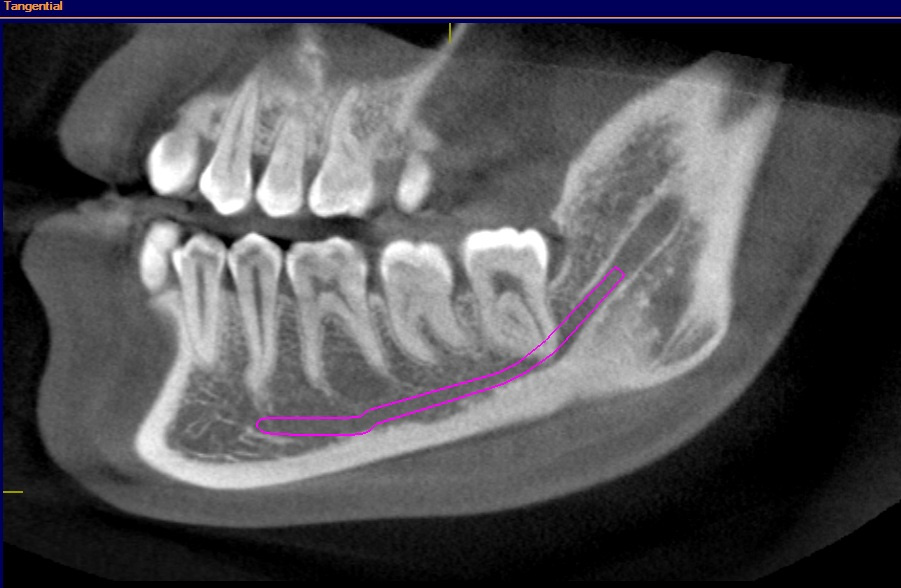

All molar teeth were evaluated in 3 planes (sagittal, axial and coronal) to determine the shortest linear distance between the root apex and the superior cortical border of MC (Figure 1). Distances <1.00 mm were classified as very close to MC (Figure 2).28 Distances ≥1.00 mm were considered distant from MC (Figure 3).28 When the root apex was in intimate contact with or invading MC, the distance was recorded as 0 mm (Figure 4).

Overall, 284 (10.5%) mesial roots were in intimate contact with or invading MC, 80 (3.0%) were very close to MC, and 2,328 (86.5%) were distant from MC. A total of 328 (12.2%) distal roots were in intimate contact with or invading MC, 76 (2.8%) were very close to MC, and 2,288 (85.0%) were distant from MC (Table 3).

The results of the present study demonstrated that the distal roots of second molars were not only the closest to MC, but also exhibited the highest percentage of intimate contact with or invasion of MC. Additionally, 11.4% of the evaluated mandibular molars had root apices that were in intimate contact with or invading MC. Consistent with these findings, Chong et al.19 and Oliveira et al.38found intimate associations between MC and root apices in more than 8% and 50% of cases, respectively. In contrast, Lvovsky et al. reported that 3.4% of the roots assessed in their CBCT study were in intimate contact with MC.39 These discrepancies among studies may be attributable to differences in genetic background and ethnicity across the populations examined.